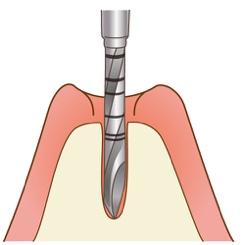

手順1:インプラント体を埋め込みます。